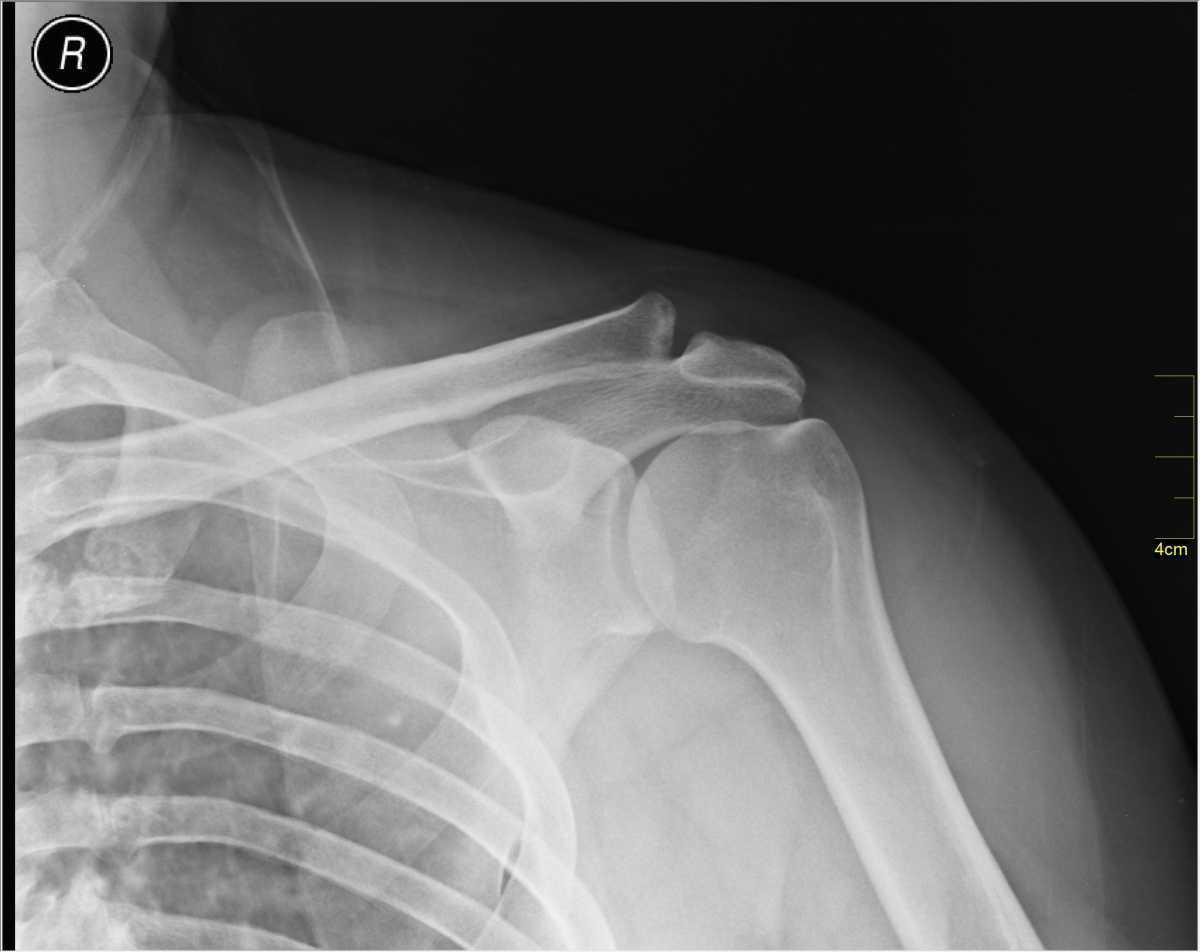

Yosi I, CC0, via Wikimedia Commons

Stade I / II :

Entorse bénigne / grave : cliniquement donne une douleur à la palpation de l’articulation acromio- claviculaire.

Stade III : Traitement orthopédique avec immobilisation 3-4 semaines.

Si stade IV-V : Avis chirurgical, car parfois geste chirurgical…même s’il est de plus en plus discuté car bonne évolution fonctionnelle malgré persistance de la déformation (séquelles esthétiques uniquement).